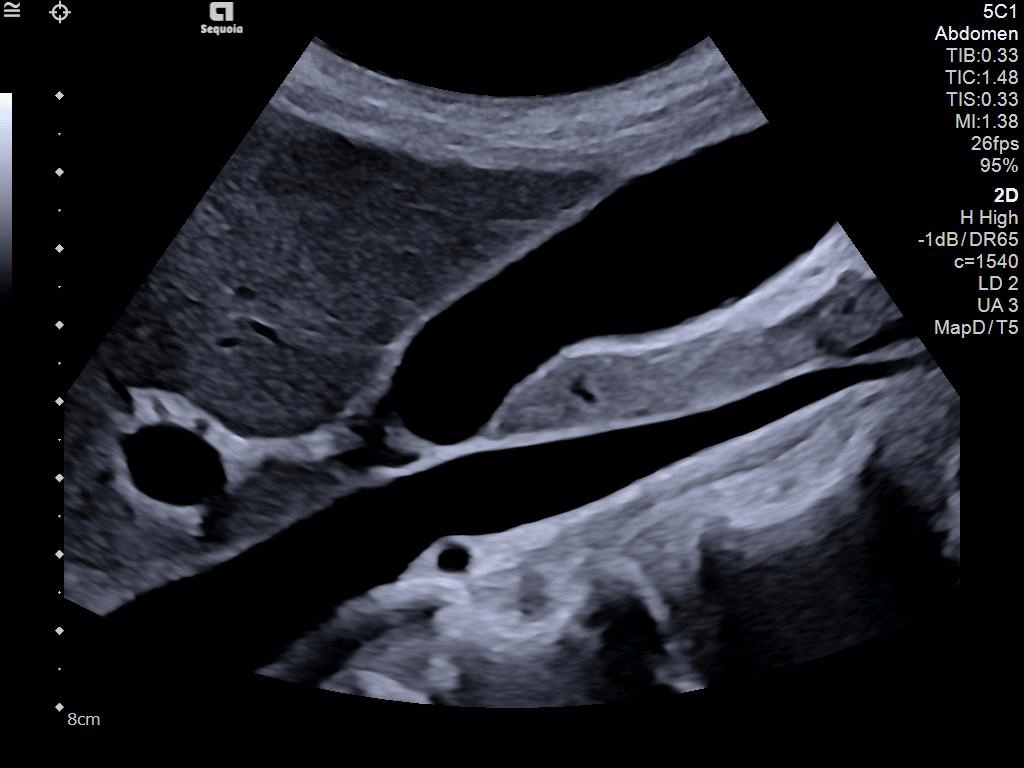

A clearer, deeper perspective with optimal acoustics for each clinical use case. Expand your assessment with advanced tools that take ultrasound beyond its traditional role.

- AI Abdomen automatically recognizes and labels 17 anatomical views and 12 routine measurements.